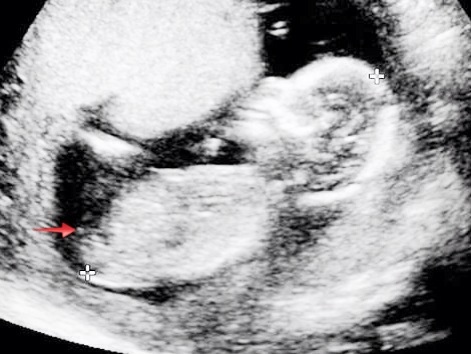

My confirmed girl pics at 12 weeks, 15 weeks and 17 weeks...

Attachment 13334